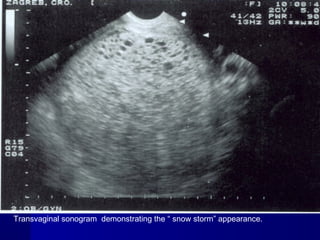

A sonographic findings of a molar pregnancy. The

characteristic “snowstorm” pattern is evident.

Transvaginal sonogram demonstrating the “ snow storm” appearance.